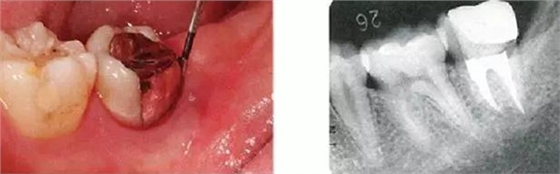

●與外傷相關(guān)的附著喪失①

右下4牙冠牙根破折案例。照片是破折前4個(gè)月拍攝的。牙周袋深度為3mm以下,牙周組織為正常狀態(tài)(右下5是以前由智齒矮小齒移植而來)。破折后,舌側(cè)咬頭破折至傾斜的牙根處,破折片與牙齦相連。

去除破折片進(jìn)行了修復(fù)治療。3年后,上頜腭側(cè)有6mm、近中有4mm的牙周袋。X片可觀察到嚴(yán)重的骨吸收現(xiàn)象??赏茢喑鍪瞧普垡鸬母街鴨适?。